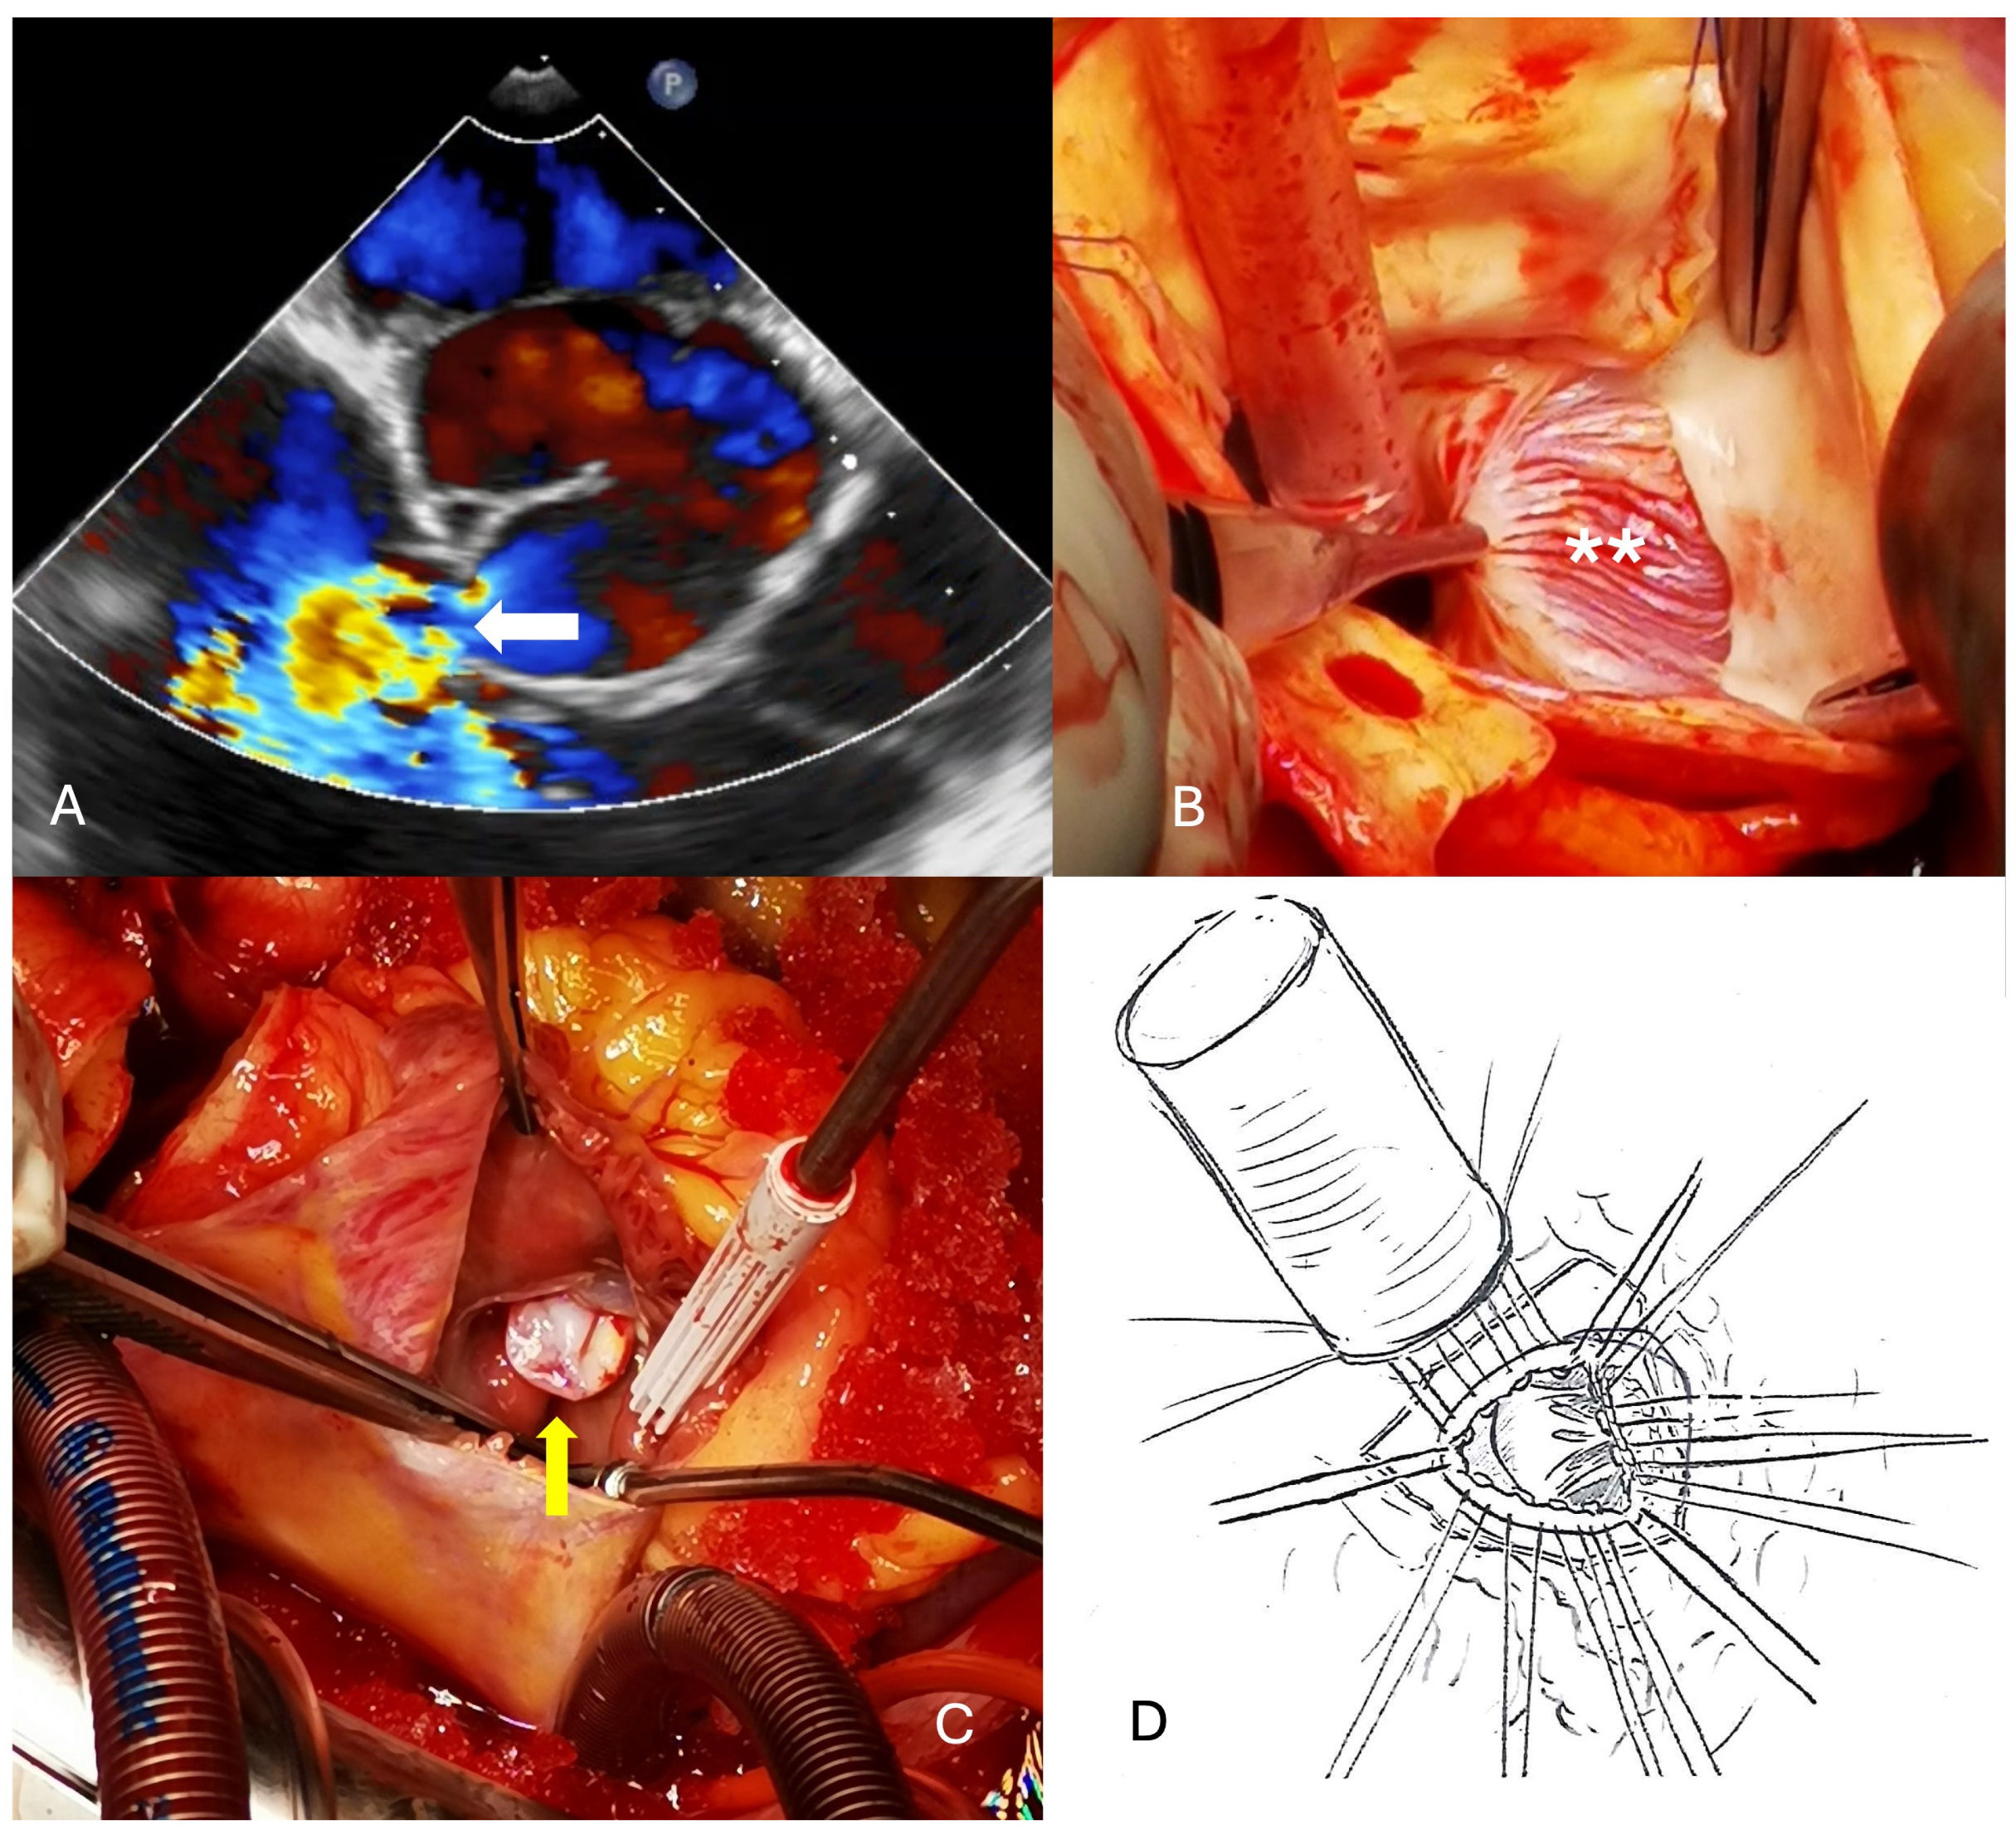

The aorta was transected to better expose the aneurysm that was located below the right coronary ostium. Closure of the cavity was performed using a xeno-pericardium patch with special attention to preserve the geometry of the aortic valve and the commissures. The proximal (ventricular-sided) suture plane was chosen at the level of the anulus, while the distal (ascending aorta-sided) suture line was performed at a level where the aortic tissue was again pretty normal under the right coronary ostium (Figure 3). Because the ascending aorta was of fragile quality and moderately dilated (45 mm), it was replaced with a short vascular graft of 30 mm diameter. Before weaning from cardio-pulmonary bypass, the left atrial appendage was closed with a clip of 40 mm in size.

Figure 3. (A) Large aneurysm in the right sinus of valsalva (white *). (B) The aorta has been transected for better visualization, and the defect closed with a patch of xeno-pericardium (white arrow). This patient received supracoronary aortic graft replacement as well. (C) Cartoon with the patch closure below the right coronary artery.